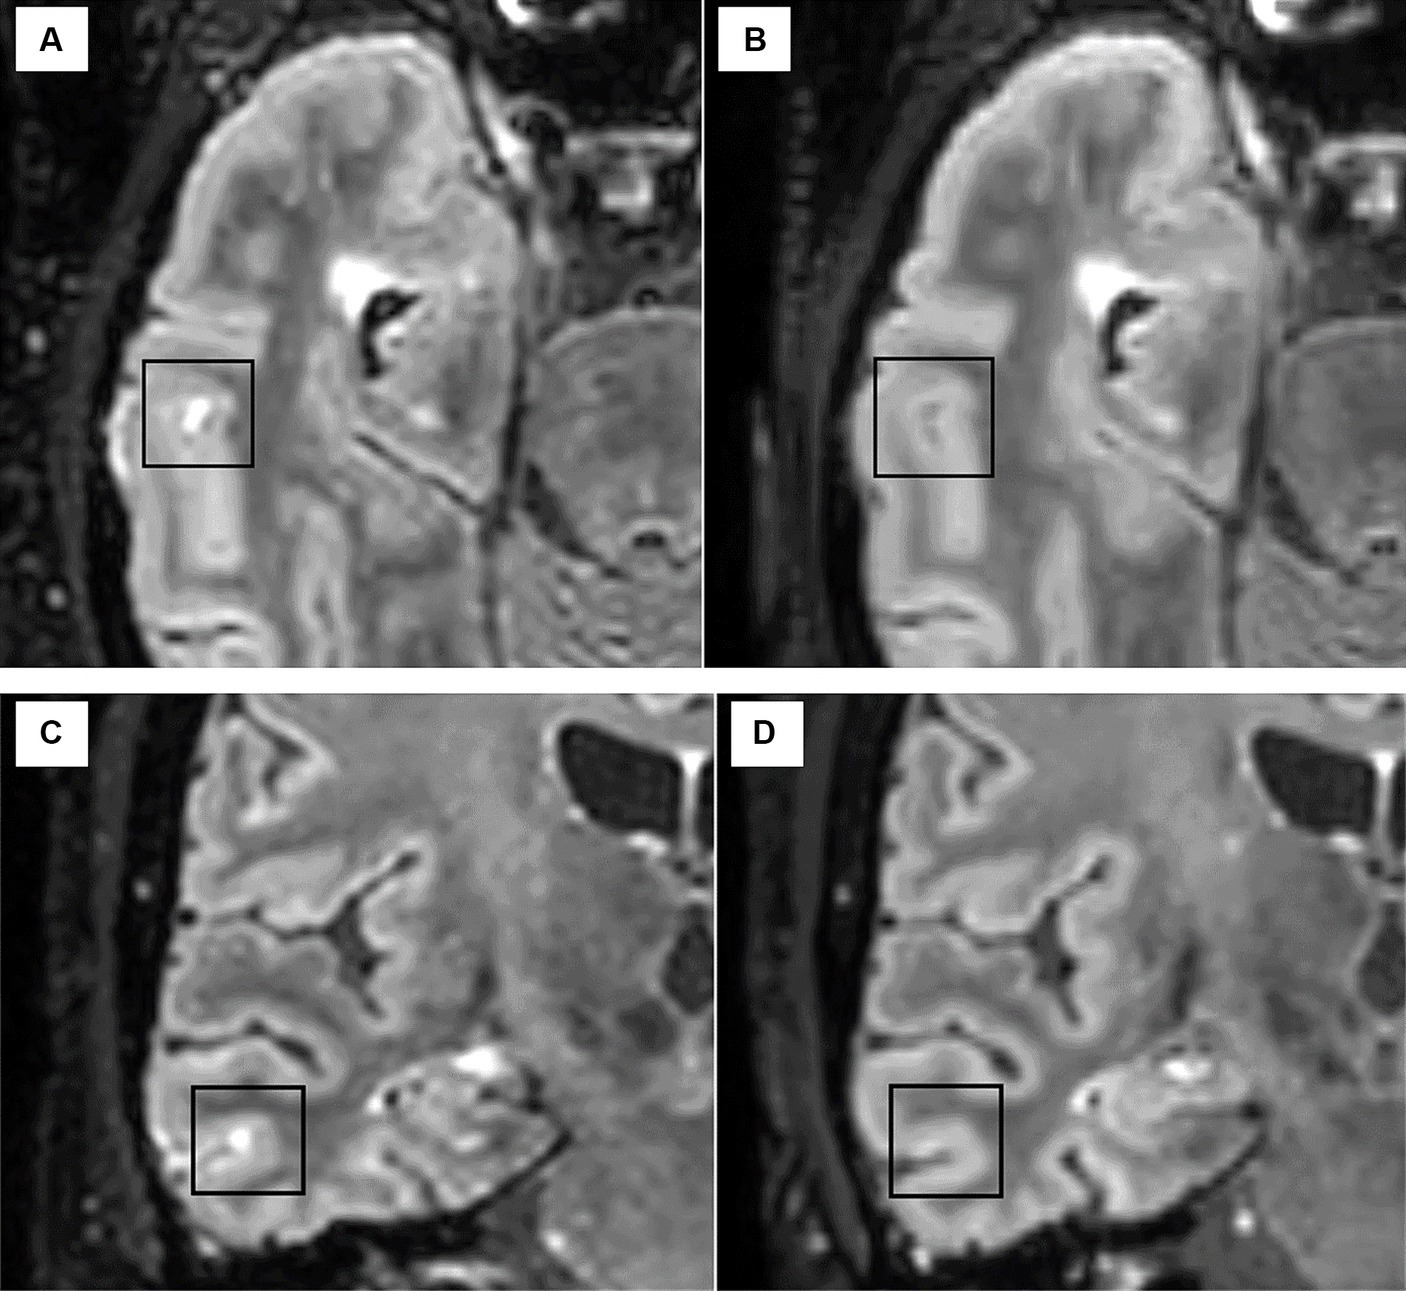

In AHSCT patients, the disappearance of one LME detected in the baseline scan was observed in one/four cases at month 6 after AHSCT (Figure 4), and the number of LMEs remained stable at a subsequent exam taken 6 months later. The number and morphology of LME were unchanged at follow-up MRIs (6 and 12 months after AHSCT) in the remaining three patients.

Figure 4

The disappearance of one LME focus was observed in one patient after AHSCT from the pre-treatment scan [axial (A) and coronal (C)] to the MRI scan taken at 6 months after AHSCT [axial (B) and coronal (D)].

No changes in the number of LME (median 1, range 1–2) were observed in the four patients from the MS CTRL group in the follow-up MRI scan.